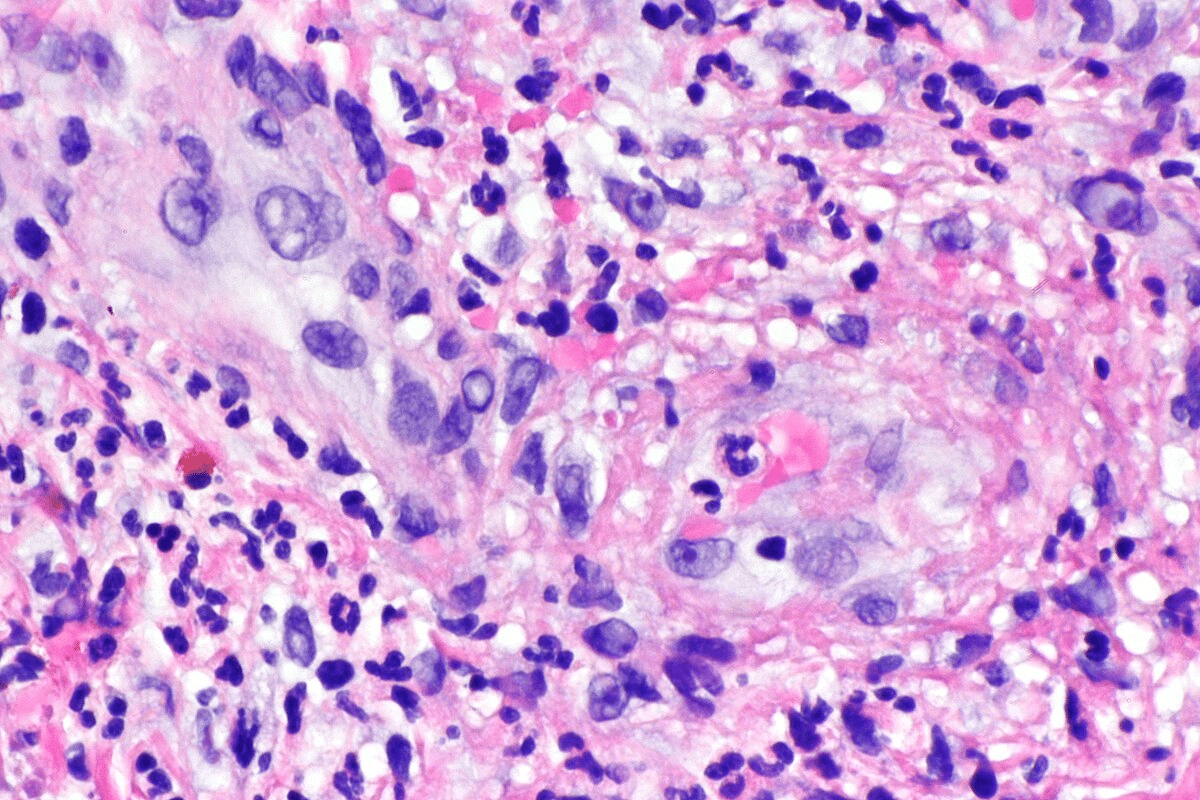

Tissue Biopsies: Confirming Necrotizing Vasculitis

Tissue biopsies are vital to confirm P-ANCA vasculitis. We take samples from affected areas like the kidneys or lungs. These show necrotizing vasculitis through histology.

Biopsy results confirm the diagnosis and show how much damage there is. This helps us decide on treatment and predict how the patient will do.